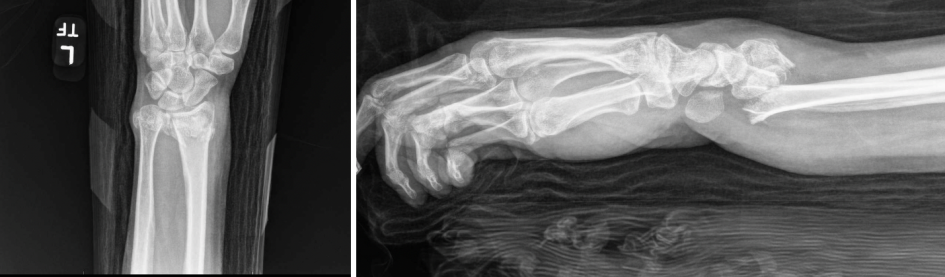

The patient was a healthy 35-year-old schoolteacher who presented with left shoulder, elbow, and wrist fractures after a fall from a horse. The patient had no pertinent past medical history and no prior orthopedic surgeries. Imaging of the left upper extremity revealed a comminuted proximal humerus fracture, terrible triad elbow fracture dislocation, and distal radius fracture with carpal tunnel syndrome (Fig. 1).

Figure 1: Pre-operative lateral (left) and anteroposterior (right) left wrist X-rays.